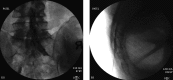

Figure 13.

Figure 13.. A and B: Sacroiliac Joint Intra-Articular Injection Antero-Posterior and Lateral Views

Note the angle of the needle in lateral view, parallel to the joint.